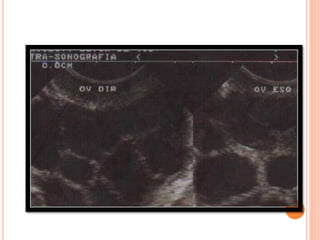

HIPERESTIMULAÇÃO OVARIANA

•2 a 3º dia após menstruação- US (fol. antrais)

•-Doses de gonadotrofinas: de acordo com características,

idade da paciente.

•FSHr, FSHu ou HMG

•hCG- 3 ou mais fol. > que 18mm e endometrio 8mm

• Bloqueio hipofisário- agonistas e antagonistas de GnRH

(21º dia do ciclo anterior)

PUNÇÃO FOLICULAR PARA FIV E ICSI